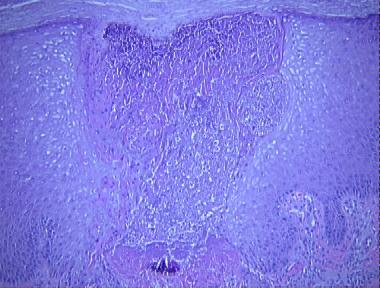

reactive perforating collagenosis

Histologic Features